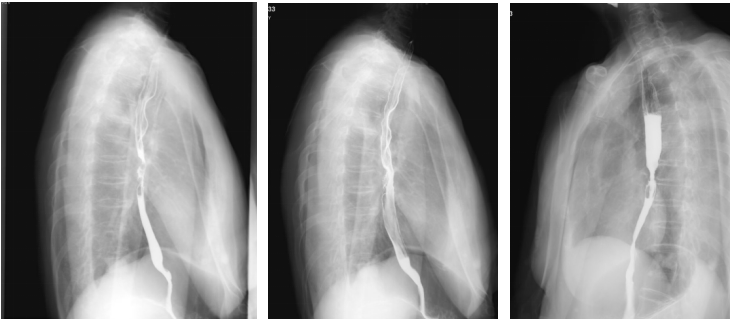

上消化道钡剂造影(2020-08-14):相当于胸7-9椎体水平的食道见范围长约35mm的狭窄段,管壁僵硬,粘膜皱襞破坏、中断,轮廓不光整,可见偏心性充盈缺损及小刺状龛影,狭窄段以上食管轻度扩张,对比剂排空延迟,余食道壁柔软,粘膜规则,未见充盈缺损及龛影,未见异常狭窄及扩张,贲门结构正常,开闭自如。

最佳疗效评估:2022-10-13胃镜:进镜至食管中段距门齿30cm处环形狭窄,所见食管上段黏膜充血水肿。